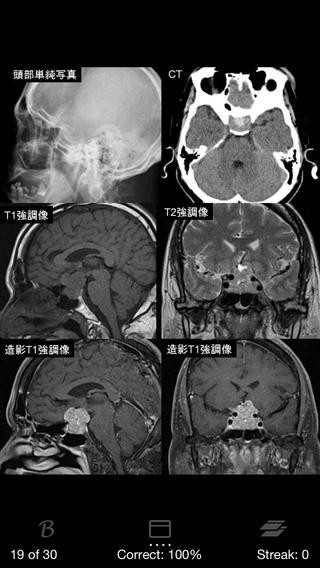

5.脳腫瘍日常臨床(1,400円)

引用元:https://itunes.apple.com/jp/app/id596370666?mt=8&ign-mpt=uo%3D4

レジデントの先生方、専門医の先生方を対象としたアプリです。

代表的な脳腫瘍30疾患に対するQ&Aと参照用データが、

全9章、180ページにわたって収録されています。